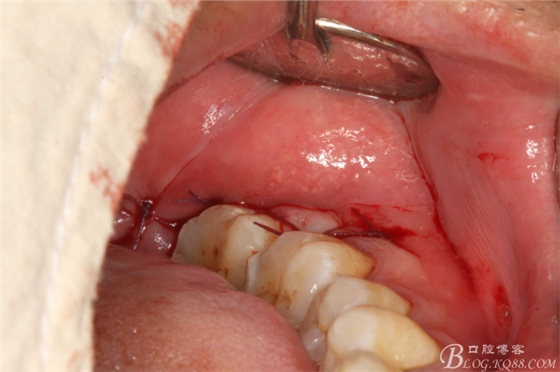

圖8. 取出后的38拔牙窩

圖9.生理鹽水沖洗拔牙窩

圖10.創(chuàng)口內(nèi)放置膠原蛋白海綿

圖12.縫合